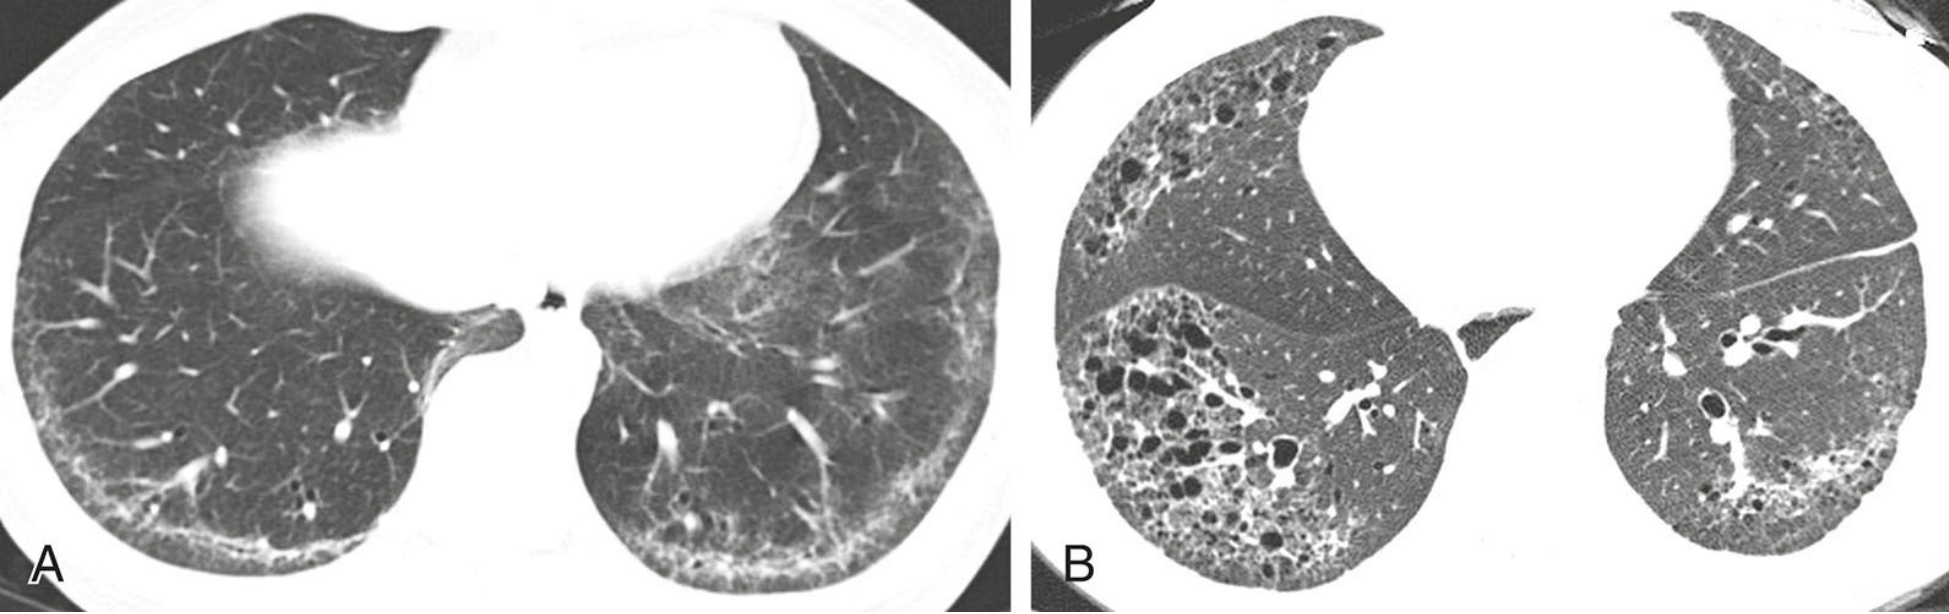

4ed145de8659ac6e2d3cf4b938bce9e7.png

脱屑性间质性肺炎(DIP)的分布的典型表现。

经上肺(A)、中肺(B)及下肺(C)层面的HRCT显示肺外周及肺基底分布的GGO。矢状位重组图像(D)亦显示该征象。注意.该吸烟患者肺上叶的肺气肿。